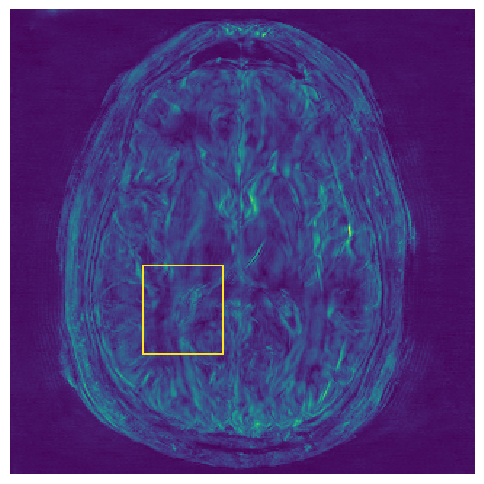

5.2 Uncertainty Assessment

We calculated the mean value of the std. maps, obtained by our method and the Monte Carlo Dropout method, for all images in the inference set and utilized it as an uncertainty measure. The correlation between these uncertainty measures and reconstruction error (MSE) is depicted in Fig. 4. Our NPB-REC uncertainty measure exhibits a higher correlation with the Reconstruction error compared to Dropout (Pearson correlation coefficient of r=0.93𝑟0.93r=0.93italic_r = 0.93 vs. r=0.89𝑟0.89r=0.89italic_r = 0.89). Further, fig. 4LABEL:sub@fig3:c demonstrates our uncertainty measures correlate better with the acceleration rates used during acquisition. These outcomes, in turn, indicate the ability of our uncertainty measure to detect unreliable reconstruction performance. It is worth mentioning that the strong linearity of the correlation exhibited was preserved even for higher acceleration rates and when we repeated the same experiments on the knee test set (in all cases we obtained r>0.92𝑟0.92r>0.92italic_r > 0.92).

Fig. 5 presents the uncertainty values measured in the cases of anatomical and undersampling mask distribution shifts. For the anatomical distribution shift, we considered the following scenarios: brain test set when the predictive model is trained on brain images as well (B-B), the same model tested on knee data (K-B), training and testing the model on the knee dataset (K-K) and the same model tested on brain data (B-K). Our uncertainty measures were significantly higher for the out-of-distribution cases compared to the within-distribution cases for both anatomical and undersampling mask distributions. In contrast, the uncertainty measures of Dropout method don’t show a significant difference in the case of anatomical shifts from knee to brain (see top-right part in Fig. 5).